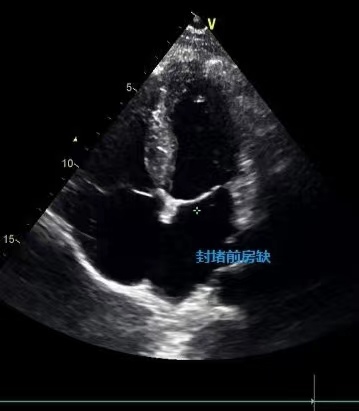

前几天值班时碰到一位妈妈带两个孩子来做心脏彩超检查,问其原因,说是自己前两年发现房间隔缺损,然后做了封堵,最近就想着两个孩子会不会被遗传呢,带来检查一下吧!(P:结果显示未见明显异常)

房间隔缺损怎么治疗呢?现在的治疗方法包括两种,一种是微创手术介入治疗,通常叫房间隔封堵术,是通过静脉穿刺,用一个封堵器,把缺损的洞堵起来,但是要求房间隔缺损的周围有足够长的残端,能够支撑这个封堵器,目前房间隔缺损的封堵,只要有适应症,治疗效果很好,可免开胸之苦。如果不能做介入治疗,则需要选择开胸治疗,打开将缺损的地方补上,效果也很好,介入治疗和外科手术治疗都是根治性手术。如果没有及时接受治疗,随着疾病的发展,可能会导致肺动脉高压,心力衰竭等并发症,缩短患者寿命,降低生活质量。如果及时接受正规治疗,一般效果良好,患者的生活质量明显提高。